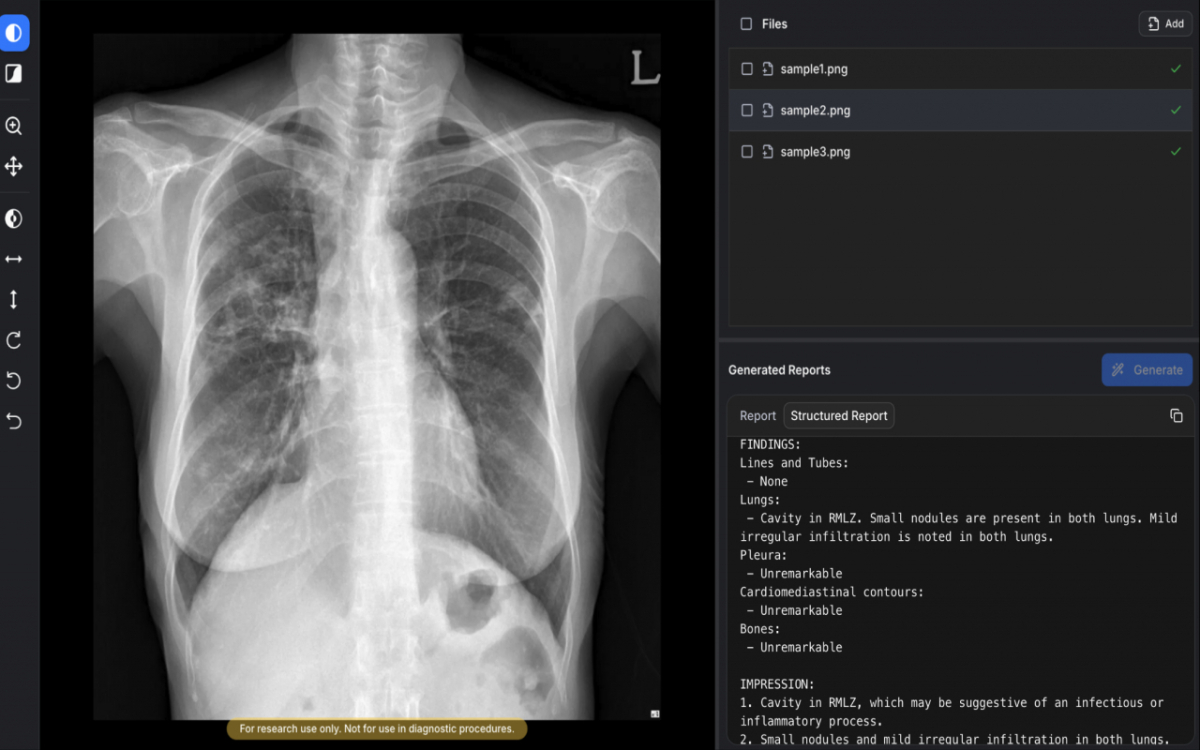

AIRead-CXR은 국내외에서 확보한 약 1400만건의 데이터를 학습해 다양한 병원 환경에서 촬영된 PA(뒤에서 앞으로 찍는 방식) 또는 AP(앞에서 뒤로 찍는 방식) 흉부X선에 대해 안정적으로 예비소견서를 제공한다.

검증된 57개 소견 및 질환에 대해 높은 수준의 판독보조 성능을 제공할 뿐 아니라 이외의 다양한 영상 소견도 해석·언급할 수 있다. 임상 현장의 실제 워크플로우를 반영해 의료진이 보다 효율적으로 판독 업무를 수행할 수 있도록 설계됐다.

공개된 임상논문에 따르면 흉부영상 전문의들이 평가한 AI 예비소견서 평균 수용도는 85%로, 비교 대상인 구글 딥마인드의 AI 모델 'MedGemma'(66.9%)를 상회했다. 환각(할루시네이션) 비율은 0.3%로, MedGemma(9.7%) 대비 우수한 안정성을 보였다.